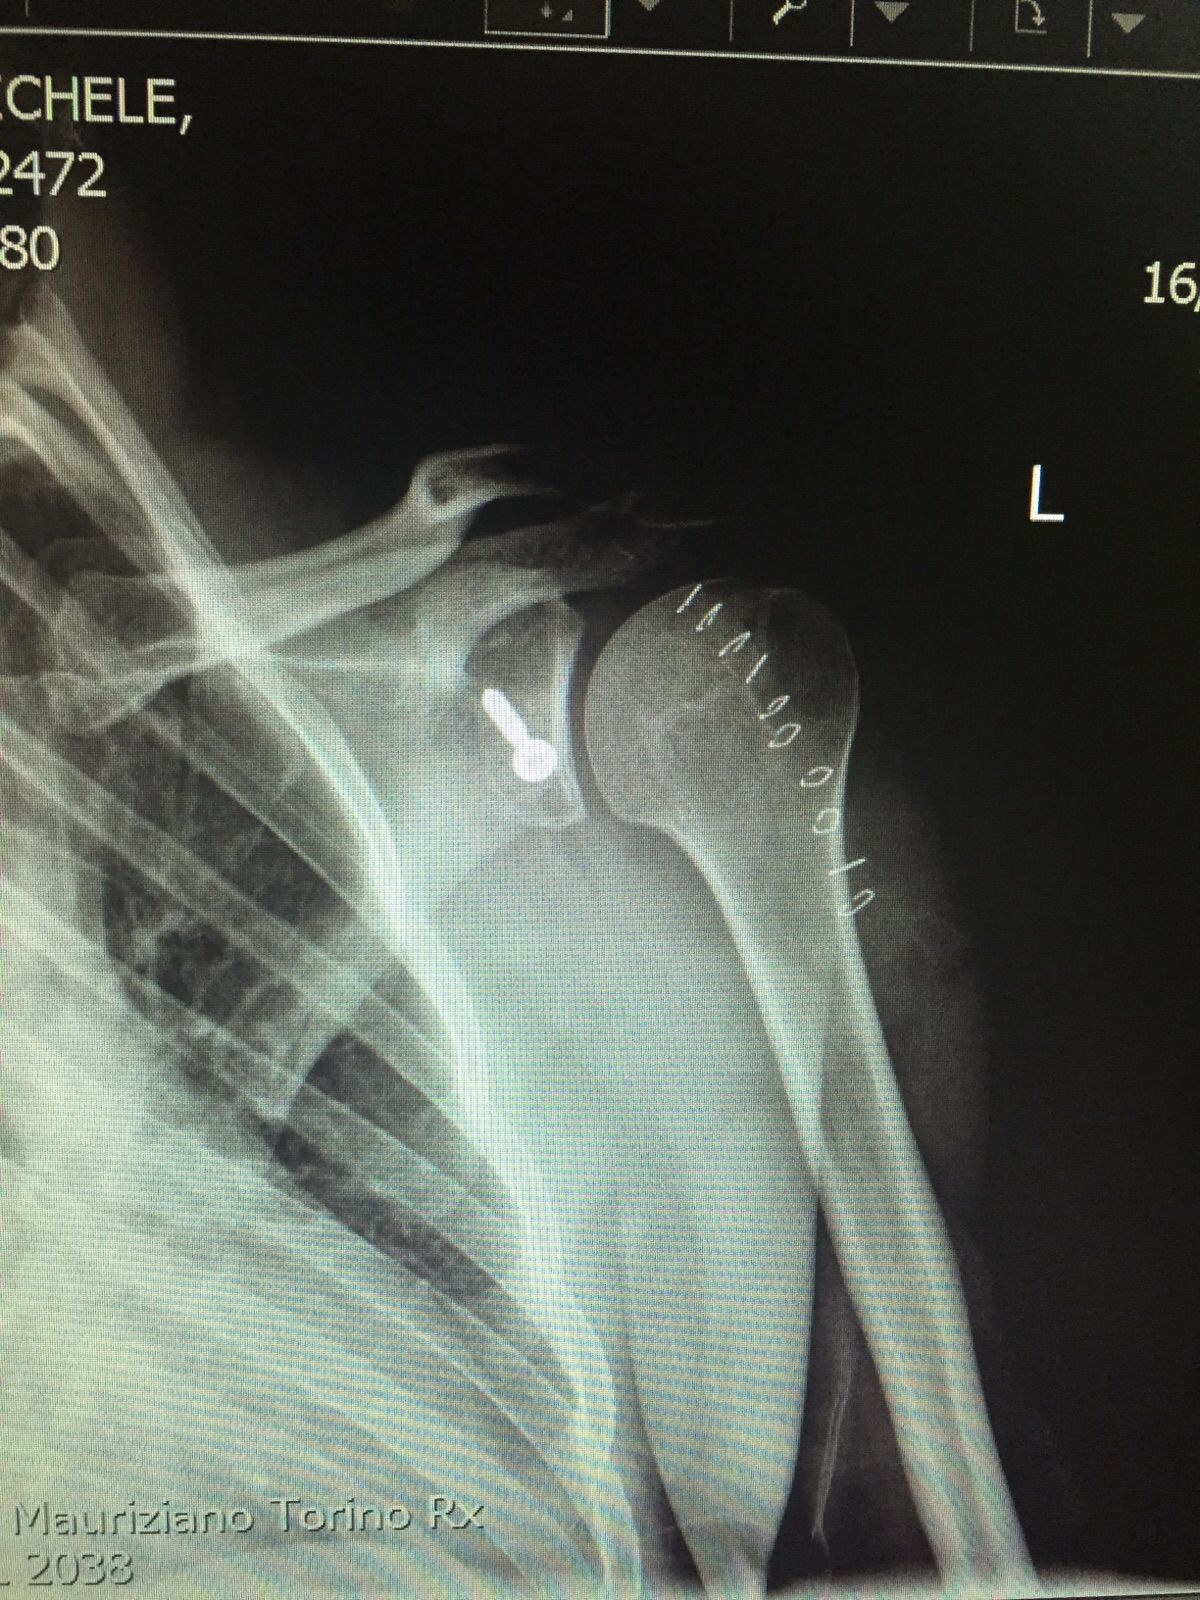

Specialista di chirurgia della Spalla, del Gomito e di traumatologia dello sport. Opinion leader e docente di fama Europea della patologia dell'arto superiore, con particolare interesse verso le ricostruzioni legamentose, l'artroscopia, la sostituzione protesica ed interventi di revisione. Gran parte della mia pratica clinica e chirurgica è attualmente il trattamento di fallimenti di altri interventi o traumi non guariti correttamente e il trattamento dell'atleta ad alto livello con patologie di spalla e gomito.

Parallelamente all'attività chirurgica di revisione ho da sempre approfondito la chirurgia mini invasiva dell'arto superiore, soprattutto sviluppando techniche chirurgiche come l'artroscopia di gomito e la fissazione esterna per le fratture di omero prossimale.

Most of my surgical practice is currently the treatment of failures of prior surgeries and post traumatic deformities. I'm also greatly involved in the treatment of high level athletes and I developed my skills in mini-invasive surgeries, especially elbow arthroscopy and mini-invasive techniques for the treatment of proximal humeral fractures.